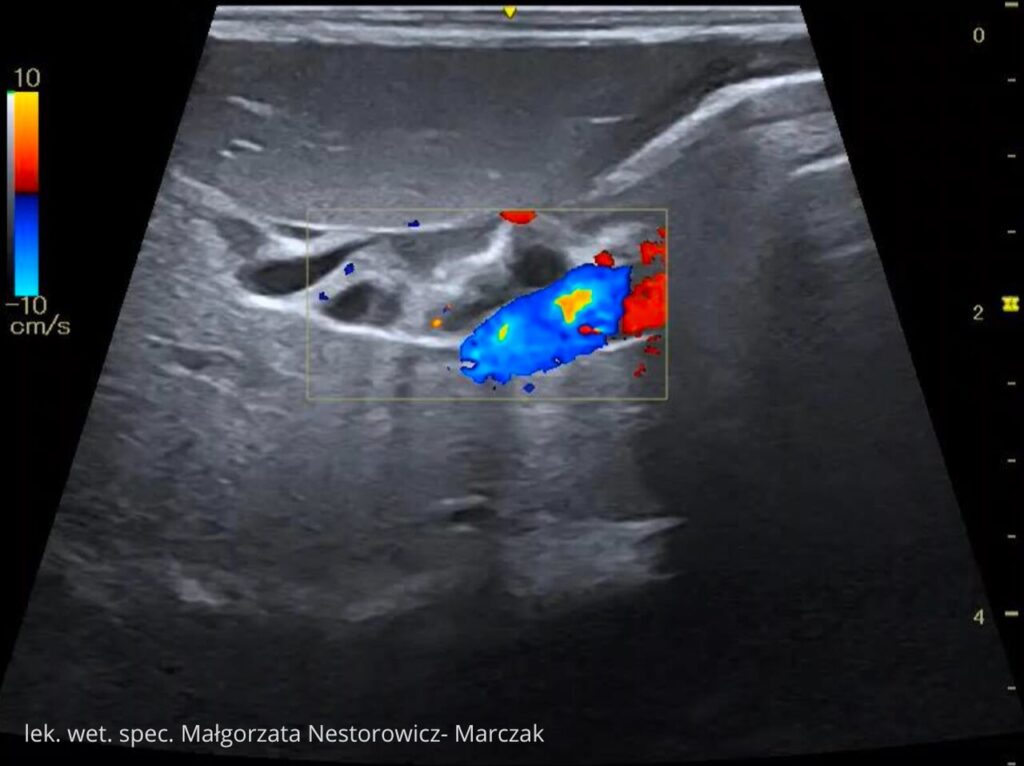

Nauka odbywa się poprzez dostęp do praktycznych nagrań wideo, przygotowanych przez lek. wet. spec. diagnostyki obrazowej Małgorzatę Nestorowicz-Marczak w oparciu o jej doświadczenie oraz pracę kliniczną.

Udostępniamy cały moduł „Wątroba i drogi żółciowe” jako próbkę kursu.

To pełnowartościowy moduł szkoleniowy (niemal 2 godziny materiału), który pozwoli Ci zobaczyć, jak w praktyce wygląda nauka w kursie. Dzięki niemu sprawdzisz:

lek. wet. spec. Małgorzata Nestorowicz- Marczak

Na co dzień pracuje z małymi zwierzętami (psy, koty) w Warszawie wykonując badania USG tkanek miękkich m.in. jamy brzusznej, szyi, klatki piersiowej. Uczestniczy jako prelegent oraz trener części praktycznej w kursach USG organizowanych dla lekarzy weterynarii.